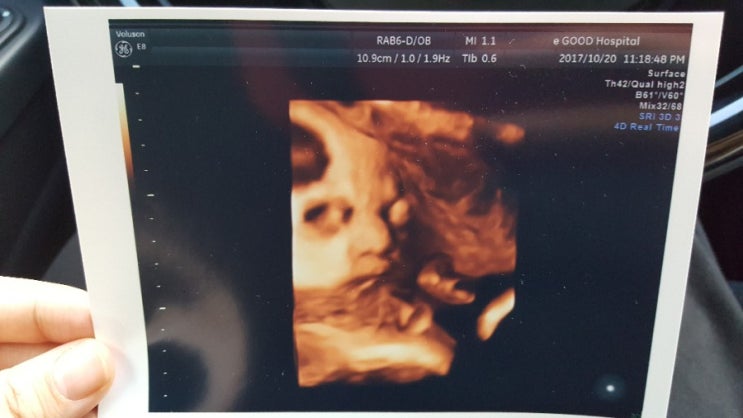

임신31주 만삭촬영/임신33주 태아몸무게/임신36주 태아몸무게/임신9개월 증상/흑백모빌 만들기